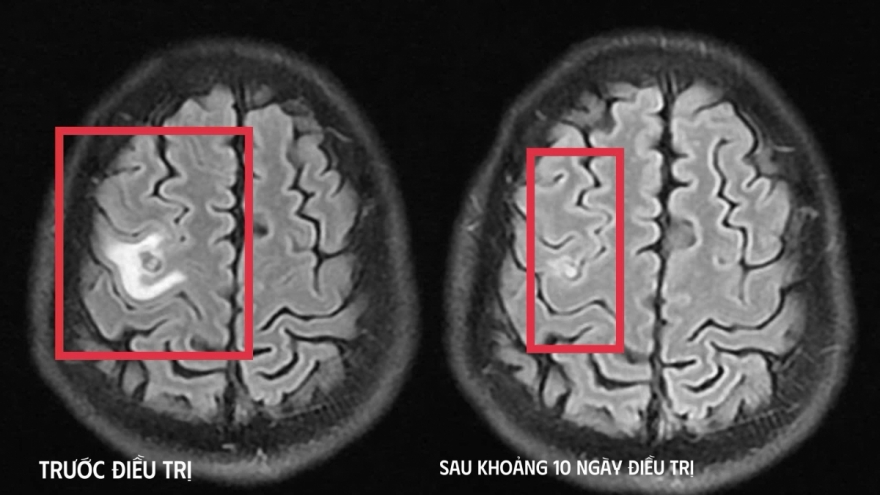

Phát hiện tổn thương não do ký sinh trùng từ triệu chứng giống u não

VOV.VN - Bệnh nhân nhập viện trong tình trạng co giật, đau đầu – những biểu hiện dễ khiến nhiều người nghĩ đến u não, song kết quả chụp cộng hưởng từ (MRI) sọ não cho thấy bị tổn thương não do ký sinh trùng.